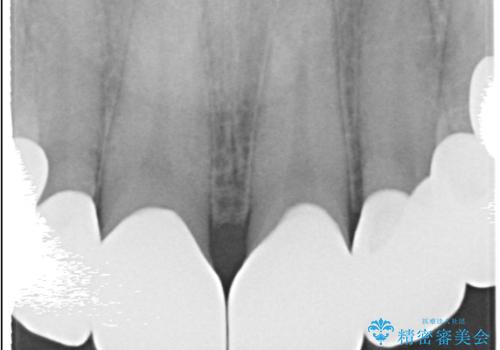

- 治療計画

治療では、まず古いクラウンを慎重に取り外し、歯肉の状態を整えました。その後、精密な型取りから患者様一人ひとりに合わせたオーダーメイドのオールセラミッククラウンを作製。金属を一切使用しないため、歯肉の変色を防ぎ、天然歯のような透明感と美しさを再現します。新しいクラウンは、歯肉のラインに合わせてぴったりと適合するよう調整し、見た目の違和感を解消。長年の悩みが解決し、自然で美しい口元と笑顔を取り戻していただけました。